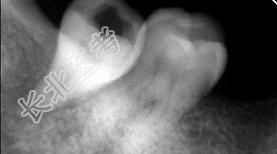

- 多项选择题关于阻生牙阻力来源正确的是 ( )

A、阻力来源于邻牙

B、阻力来源于骨组织

C、阻力来源于牙龈

D、阻力来源于咀嚼肌

E、阻力来源于对

牙